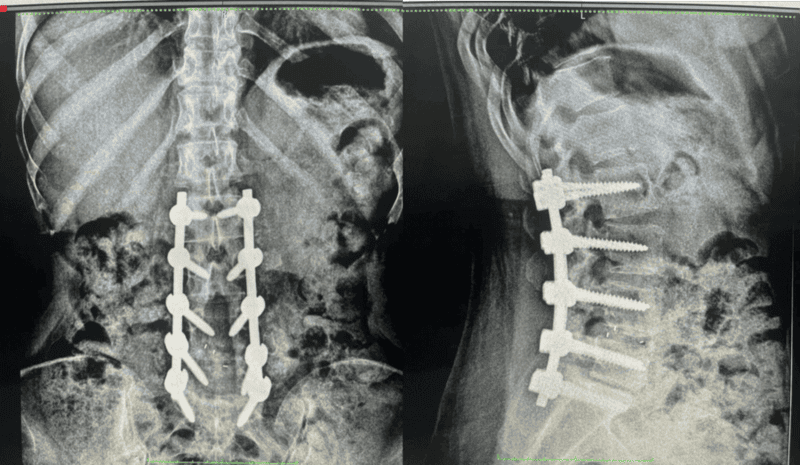

fractura de vertebras postquirurgico

• Fusión vertebral: En casos severos, puede ser necesaria una fusión vertebral para bloquear definitivamente el segmento afectado. Esta cirugía puede realizarse en diferentes tiempos. Además de la colocación de tornillos posteriores, puede requerir implantes en la parte anterior de la columna para reemplazar total o parcialmente la vértebra fracturada (corporectomía).

Tratamiento Quirúrgico de la Escoliosis (Enfoque General): La cirugía de escoliosis tiene como objetivo corregir el segmento curvado de la columna. Se realiza una realineación y fusión de las vértebras necesarias para fijar la columna en su nueva posición. Esto se logra mediante la colocación de tornillos transpediculares que se conectan entre sí con barras de metal para alinear y estabilizar la columna. En nuestro centro, aplicamos diversas técnicas quirúrgicas avanzadas para este procedimiento.